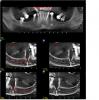

Пациент@Ка Опубликовано 27 января, 2009 Поделиться Опубликовано 27 января, 2009 (изменено) Добрый день.Во вложении результаты КТ,нужна консультация. Что дедать, как делать и где лучше.Спасибо заранее. Изменено 27 января, 2009 пользователем Пациент@Ка Ссылка на комментарий

константин Опубликовано 27 января, 2009 Поделиться Опубликовано 27 января, 2009 если сьемное протезирование- то удаление жевательных зубов на верхней и нижней челюсти, восстановление высоты прикуса, далее передние зубы под коронки и сьемный протез на верхн. и нижн. челюсть если рассматривать вариант с несъемным протезтрованием, то ко всему этому нужно добавить костнопластические операции по увеличению обьема костной ткани как на нижней , так и на нижней. ношение временых съемным протезов желательно для восстановленния физиологичного положения и движения нижней челюсти. по срокам:- съемное протезирование - приблизительно год, до сдачи окончательного протеза... - несьемное значительно удлиняется время ... Ссылка на комментарий